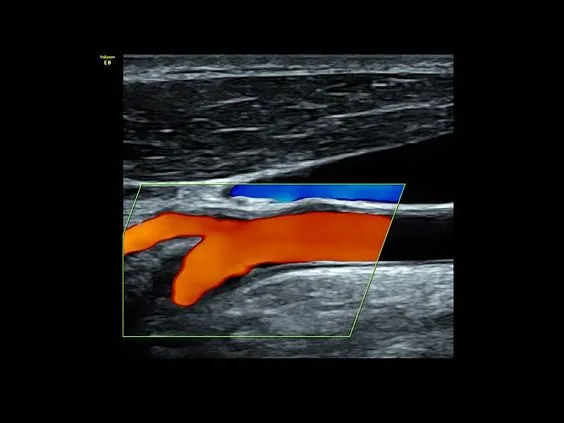

Клинические изображения

- Высокочувствительный допплер (HD-Flow).

- Высокочувствительный допплер (HD-Flow).

- Недопплеровская визуализация кровотока в B-режиме (B-Flow).

- Ангиология

- 11L-D — линейный датчик 4-10 МГц для исследования поверхностно расположенных органов и структур, скелетно-мышечного аппарата, периферических сосудов, педиатрии.

- 9L-D — линейный датчик 3-8 МГц для исследования периферических сосудов,поверхностно расположенных органов и структур, педиатрии.

- ML6-15-D — высокочастотный матричный линейный датчик 4-13 МГц для исследования поверхностно расположенных органов и структур, скелетно-мышечного аппарата, периферических сосудов, педиатрии.

- RSP6-16-D — 4D линейный датчик 6-18 МГц для исследования поверхностно расположенных органов и структур, скелетно-мышечного аппарата, периферических сосудов, педиатрии.